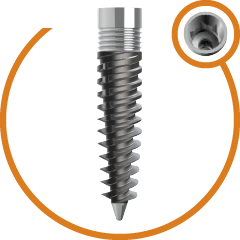

Completely Polished body of zygoma to avoid peripathogen and prevent

sinus related complication

Progressive single spiral threads. Anti- rotational cuts to improve primary stability. Higher Bone Implant contact.. More Resistance to Tensile & Compressive forces. Surface treated thread to achieve better secondary stability.